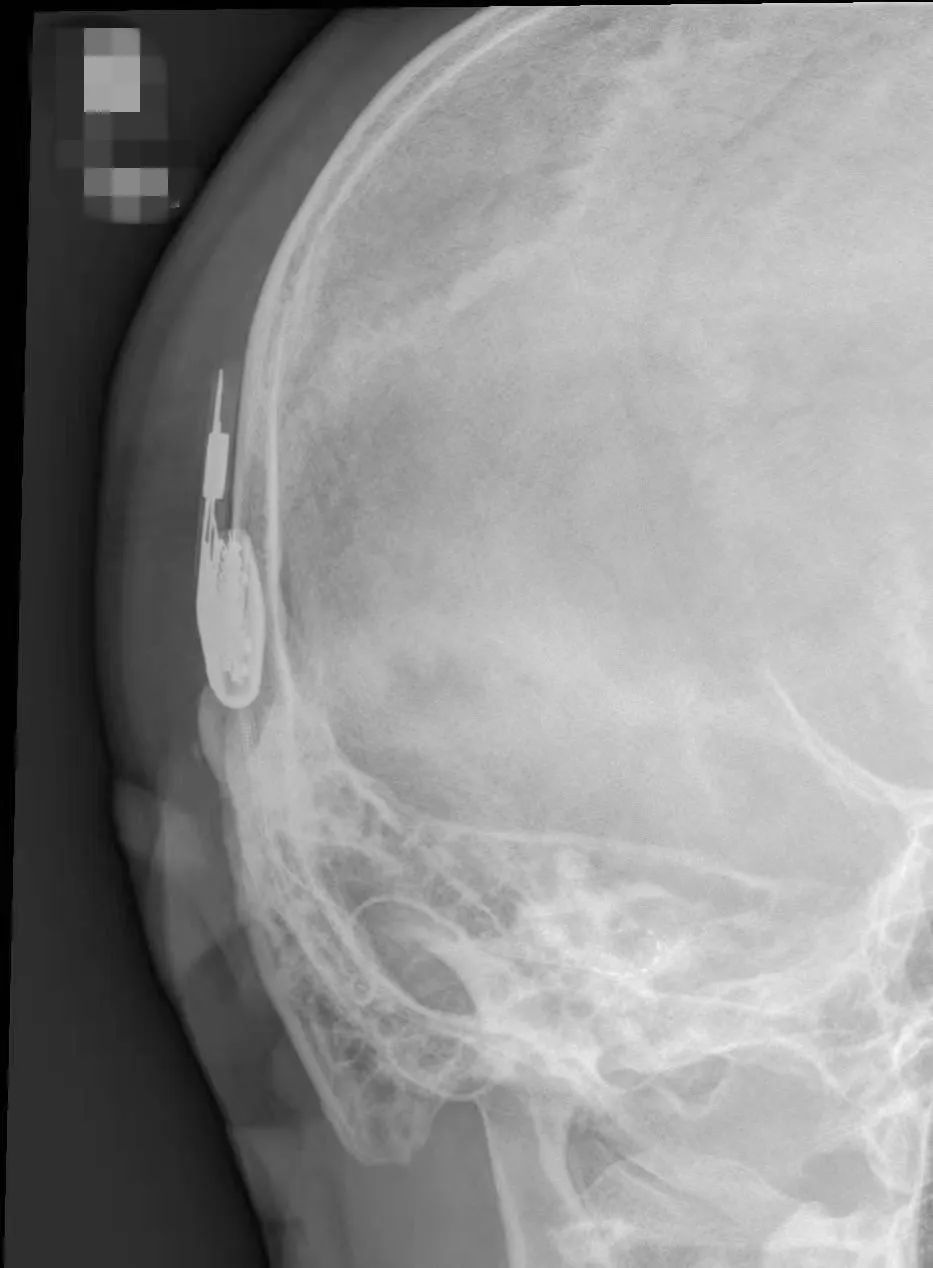

因2025年国家人工耳蜗集采政策的实施,耳蜗价格将大幅度下调,二十几万的人工耳蜗,集采价格可低至五万左右,很多患者为了享受政策红利,都在等待政策落地后再进行植入手术。既要与耳蜗骨化病变抢时间,又要考虑患者的经济压力,综合考量,王晓茜主任团队为患者量身定制了最大获益的手术方案:右侧人工耳蜗植入及左侧微创耳内镜下试探电极植入。即在右耳植入人工耳蜗的同期,左耳采取微创路径,耳内镜下内耳开窗,利用试探电极先占据左侧耳蜗底周空间,为后续左耳人工耳蜗植入实现双耳听力提供条件。基于该例病情复杂,术中耳蜗病变的不确定性,为了确保手术的顺利进行,王晓茜主任邀请广东省人民医院崔勇教授共同完成该例手术。术中发现耳蜗情况并未像术前磁共振显示的那样底转淋巴液充盈,而是大量纤维化组织,给手术增加了难度,按照预计方案,团队利用试探电极开拓双耳蜗底周植入路径,右侧人工耳蜗电极及左侧试探电极均顺利植入,术后X光片显示电极位置佳。正得益于团队充分的术前准备,最终确保了手术的成功实施。

▲术后内耳斯氏位显示电极位置佳